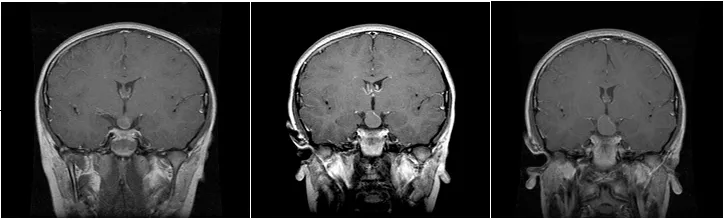

1999年7月因头痛症状发现颅咽管瘤的病例显示,在2000年1月及4月的复查中观察到肿瘤持续生长。一般而言,当颅咽管瘤侵犯鞍区和丘脑区域时,患儿通常会出现内分泌疾病、视力障碍、眼压升高、颅内压增高等症状,临床表现包括视力模糊、头痛等。

进行性生长的颅咽管瘤在颅内持续扩张,可侵犯侧脑室、第三脑室和室间孔区域,并与下丘脑紧密相连,可生长在垂体柄的任何位置。肿瘤生长初期通常占据鞍区,随着进一步发展,会向鞍上区域生长,导致第三脑室底部出现受压凹陷。